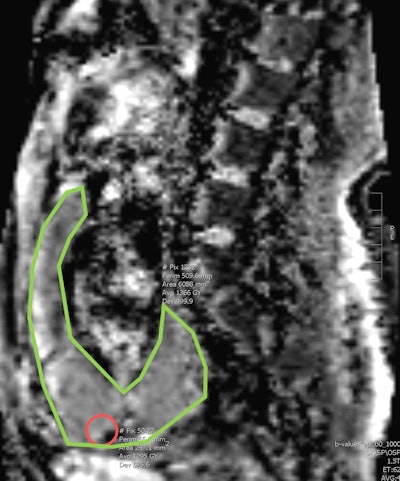

ADC values were obtained from the area above the bladder and the entire placenta on a midline sagittal image by two readers. Heterogeneity of the placenta and placental dark bands were also noted. A pathological diagnosis was obtained from the medical records. Texture study of a sample size of 33 images was also analyzed using a radiomics program (LIFEx) by a single reader.